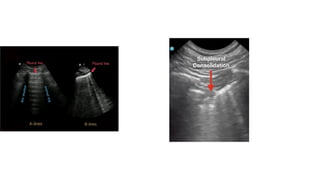

PATHOLOGICAL LUNG SIGNS

• B-lines represent discrete laser-like vertical hyperechoic lines that

arise from the pleural line and extend to the bottom of the screen.

These lines are consistent with interlobular pulmonary edema and

can be found in both ARDS and cardiogenic pulmonary edema.

• Dynamic and static air bronchograms which consist of

hyperechoic punctiform elements within the lung parenchyma can

be used to diagnose consolidation and atelectasis, respectively.

PULMONARY EDEMA AND FIBROSIS

• When the pulmonary interstitium

thickens (secondary to fibrosis or

fluid), B-line artifacts replace the

normal A-lines

• B-line artifact consists of well-

defined, laserlike, vertical,

echogenic lines arising from the

pleural line and extending to the

bottom of the image.